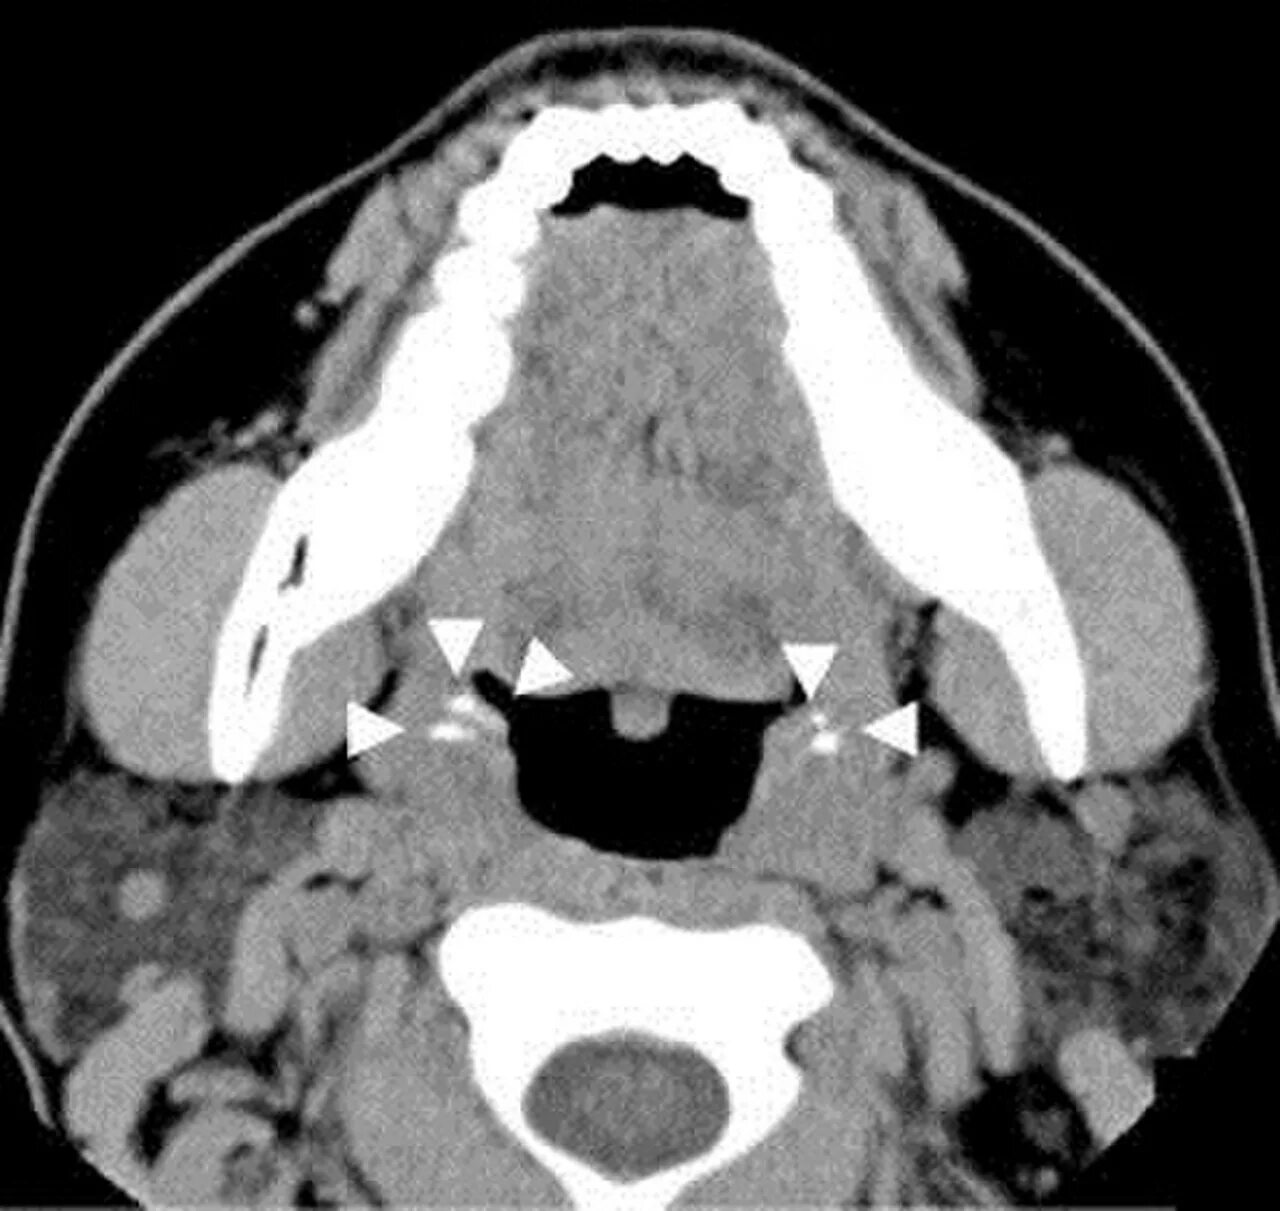

Миндалины на кт